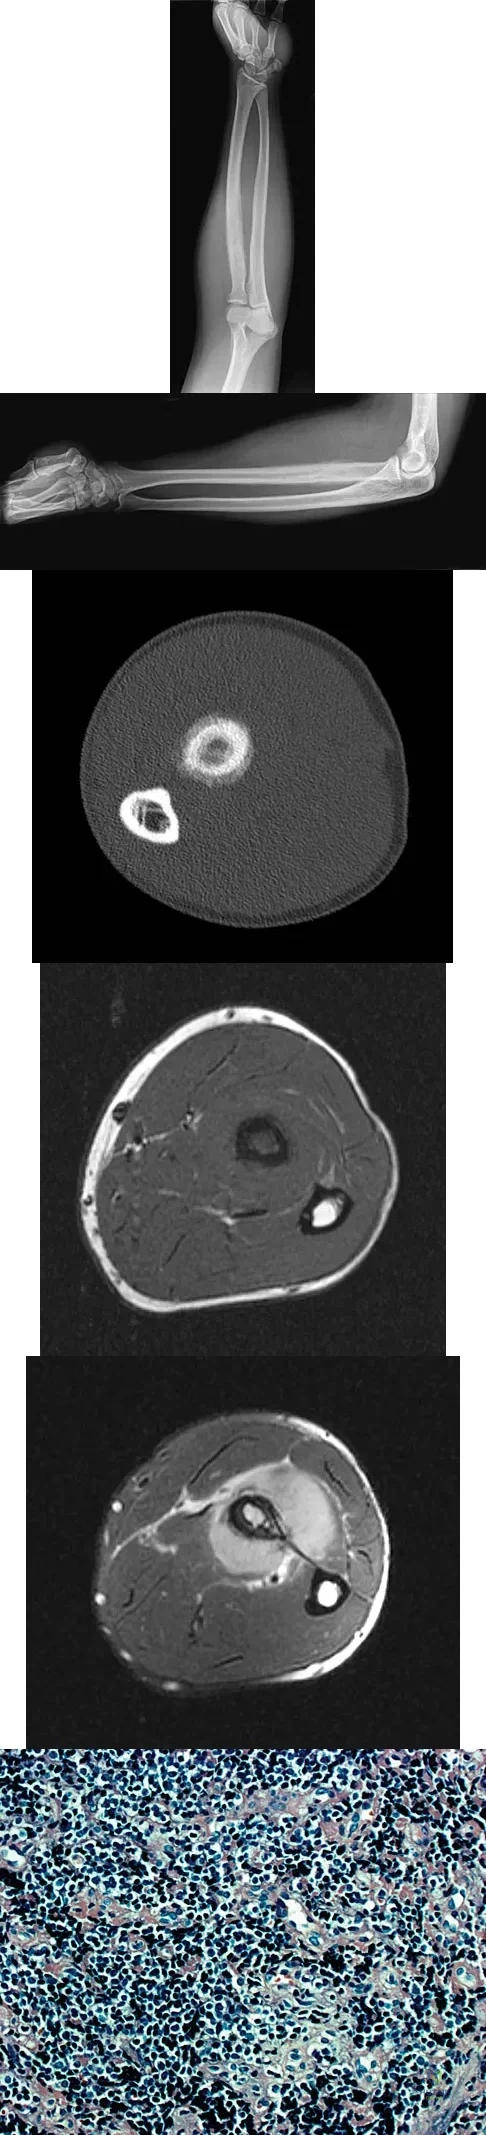

Question 20High Yield

A 19-year-old man has had pain and swelling in his left forearm for the past 8 months. Laboratory studies show a mildly elevated WBC count and erythrocyte sedimentation rate. Radiographs are shown in Figures 58a and 58b, a CT scan is shown in Figure 58c, and T1- and T2-weighted MRI scans are shown in Figures 58d and 58e, respectively. A biopsy specimen is shown in Figure 58f. Immunohistochemistry demonstrates that the lesion is negative for leukocyte common antigen (CD34). What is the most common cytogenetic translocation associated with this lesion?

Explanation